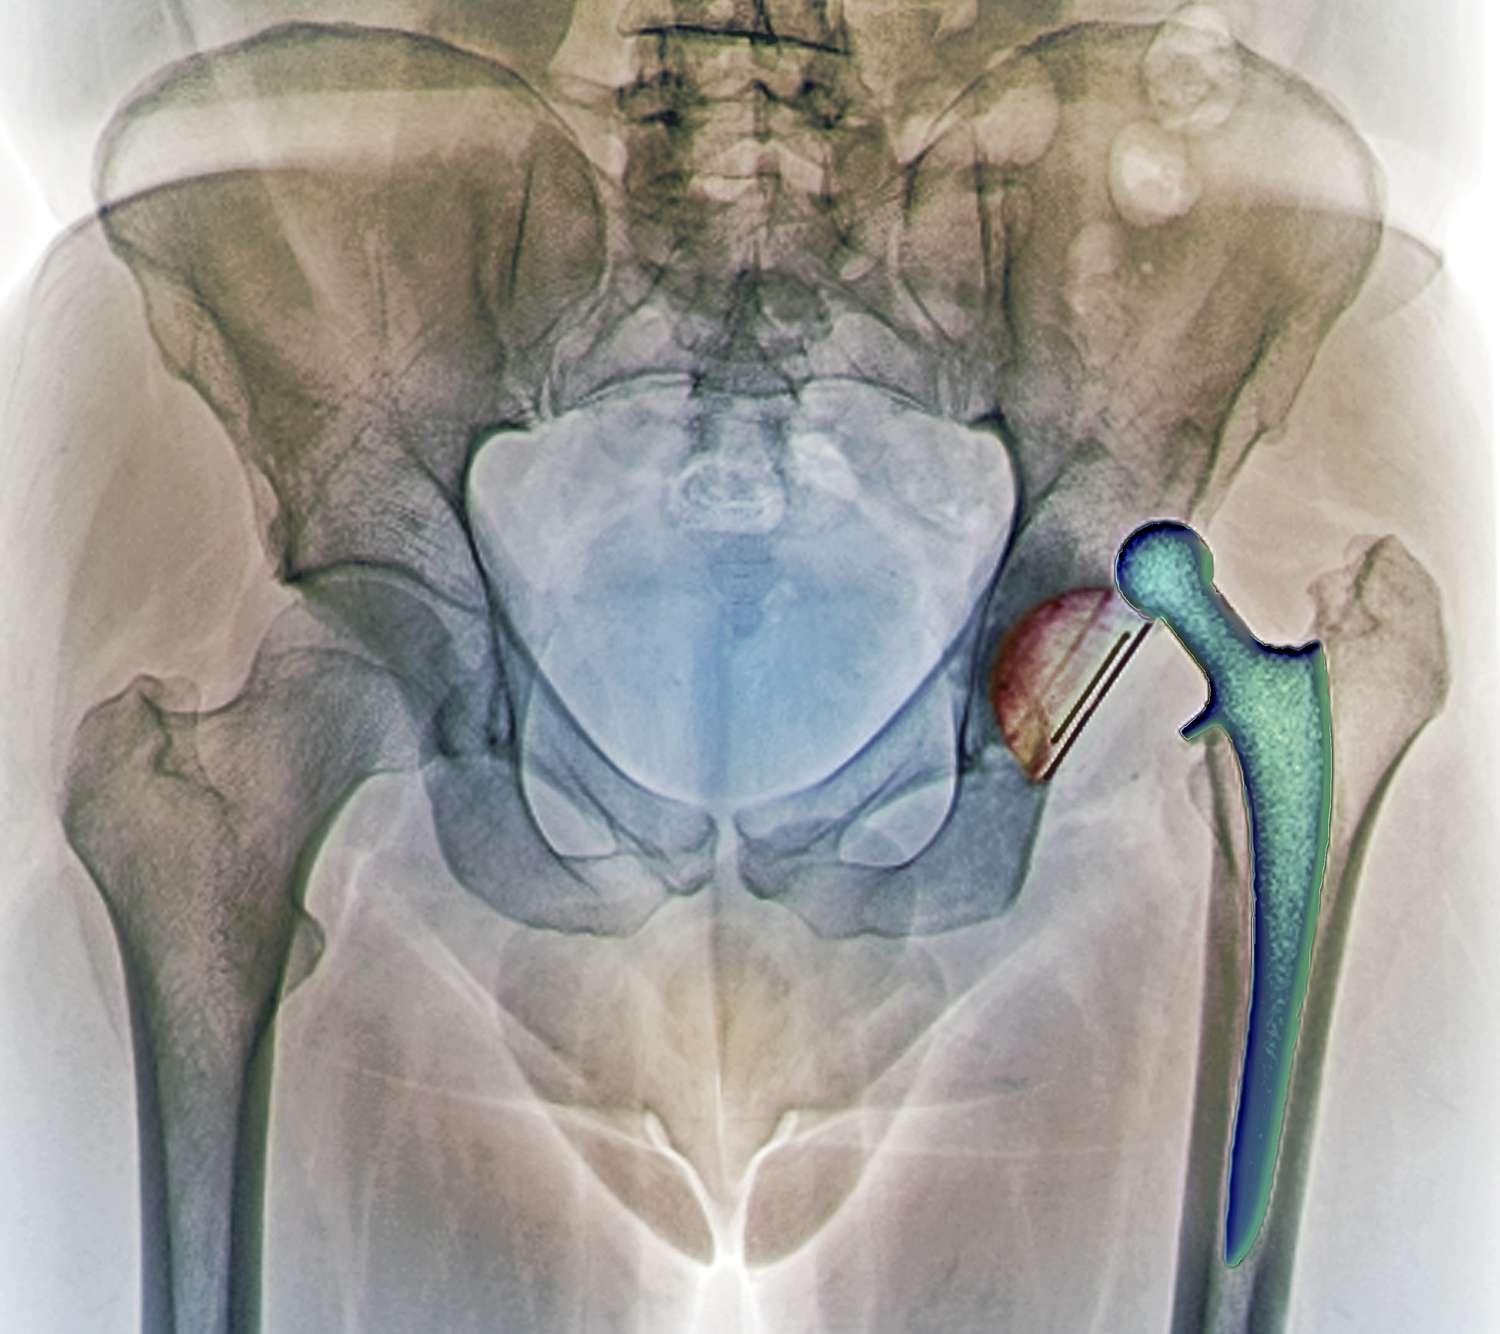

Kalça çıkığı ameliyatı sonrası düzenli doktor kontrolleri, iyileşmenin doğru bir şekilde ilerlediğinden emin olmak için şarttır. Bu kontroller sırasında, röntgen ya da diğer görüntüleme yöntemleriyle eklemin durumu değerlendirilir. Ayrıca, hastanın yaşadığı herhangi bir sorun ya da ağrı da bu ziyaretlerde ele alınır. Uzun vadede, kalça ekleminin sağlığını korumak için belirli aralıklarla takip yapılması önerilir. Doktorunuz, yaşam tarzınızda yapmanız gereken değişiklikler hakkında da sizi bilgilendirecektir.